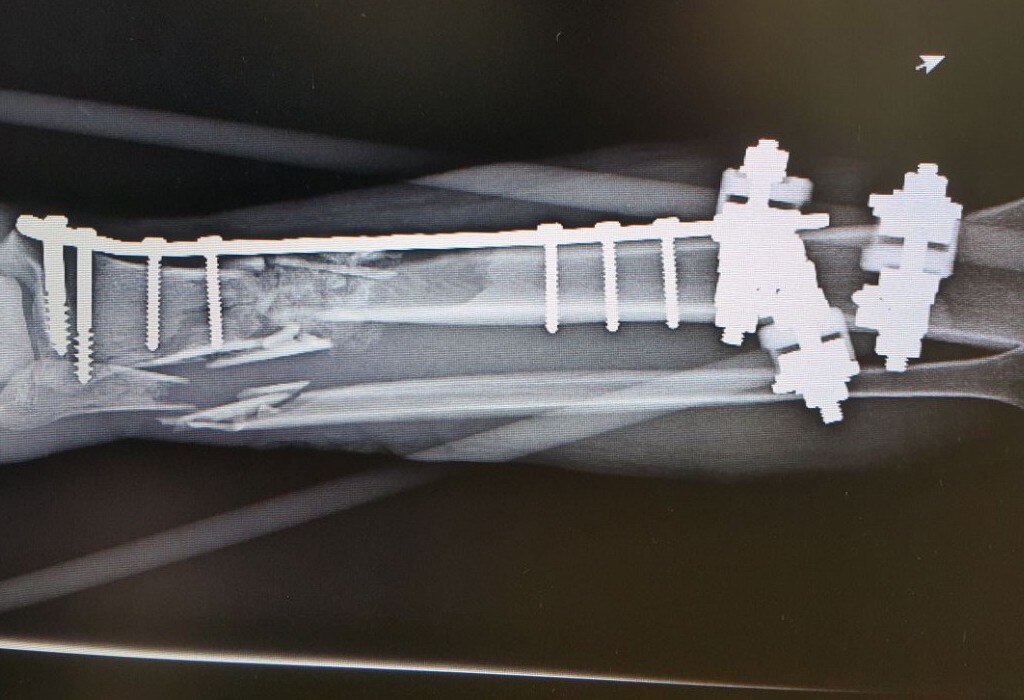

Fue aproximadamente una pérdida de 11 centímetros de hueso, por lo que al llegar al hospital se le realizaron cirugías para preservar la viabilidad de los tejidos afectados y la colocación de placas en las partes óseas.

Por la fractura expuesta, la fragmentación de los huesos y debido a que la pierna estaba unida al tobillo sólo por tejido blando, un procedimiento inmediato era la amputación, explicó el especialista en Traumatología y Ortopedia del Hospital General de Zona No. 11, Eduardo Morales Martínez, quien encabezó al equipo multidisciplinario que atendió a Luis René.

Sin embargo, se buscó la forma de salvar el miembro y mediante la recuperación de la viabilidad de los tejidos blandos se optó por el implante óseo. El doctor Morales explicó que en este caso se activó el protocolo para solicitar tejido óseo y al cabo de algunos meses se logró obtener el hueso de un cadáver apto para implantarse.

Fue necesario recurrir a un implante de hueso porque era una lesión muy extensa. No había sustento, no había hueso, no había de dónde fijar la placa. Era prácticamente una pérdida total, el pie estaba suelto y no había soporte que uniera esas dos estructuras, explicó el especialista. El riesgo de pérdida de la extremidad fue alto y el proceso de recuperación fue de aproximadamente un año.

La recuperación del hueso está al 100, ya tiene una integración radiográfica del injerto y debe continuar con el ejercicio de deambulación, puntualizó.